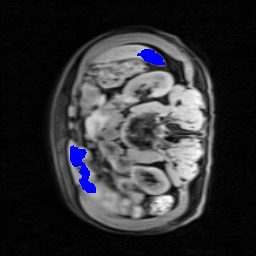

Transformers have made remarkable progress towards modeling long-range dependencies within the medical image analysis domain. However, current transformer-based models suffer from several disadvantages: (1) existing methods fail to capture the important features of the images due to the naive tokenization scheme; (2) the models suffer from information loss because they only consider single-scale feature representations; and (3) the segmentation label maps generated by the models are not accurate enough without considering rich semantic contexts and anatomical textures. In this work, we present CASTformer, a novel type of generative adversarial transformers, for 2D medical image segmentation. First, we take advantage of the pyramid structure to construct multi-scale representations and handle multi-scale variations. We then design a novel class-aware transformer module to better learn the discriminative regions of objects with semantic structures. Lastly, we utilize an adversarial training strategy that boosts segmentation accuracy and correspondingly allows a transformer-based discriminator to capture high-level semantically correlated contents and low-level anatomical features. Our experiments demonstrate that CASTformer dramatically outperforms previous state-of-the-art transformer-based approaches on three benchmarks, obtaining 2.54%-5.88% absolute improvements in Dice over previous models. Further qualitative experiments provide a more detailed picture of the model's inner workings, shed light on the challenges in improved transparency, and demonstrate that transfer learning can greatly improve performance and reduce the size of medical image datasets in training, making CASTformer a strong starting point for downstream medical image analysis tasks.